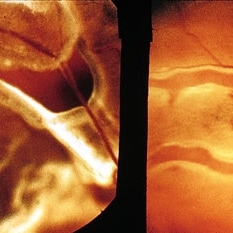

Asteroid hyalosis. These opacities may be polychromatic. Lower right view shows the histologic appearance and the birefringence of these opacities.

Condition/keywords: asteroid hyalosis, birefringence, opacities